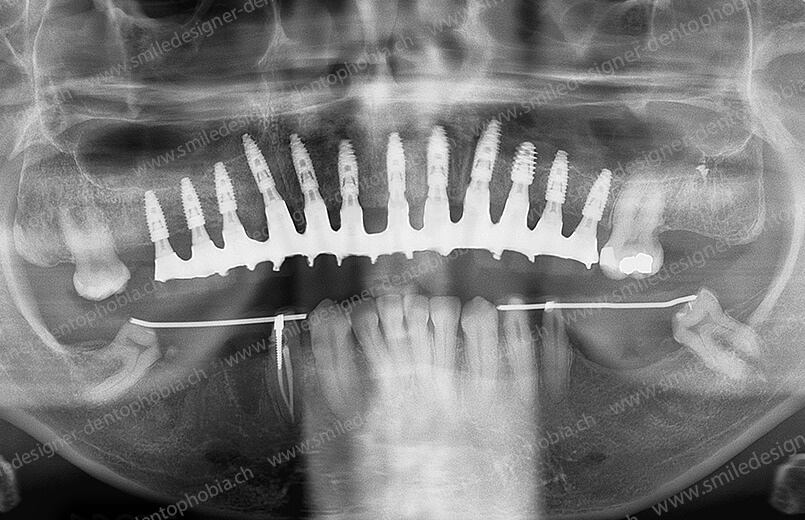

Cas clinique « GOLD STANDARD MCI » bi-maxillaire : Bridge implanto-porté sans extension postérieure (ALL ON 8/8). Version définitive des bridges avec un cosmétique en céramique.

BRIDGE RÉSILIENT PROTOTYPE DE PREMIÈRE INTENTION DE MISE EN CHARGE IMMÉDIATE 4 JOURS APRÈS LA POSE DES IMPLANTS POUR UNE RESOCIALISATION IMMÉDIATE DU PATIENT

CAS EN COURS D’OSTÉOINTÉGRATION DES IMPLANTS BI-MAXILLAIRES.